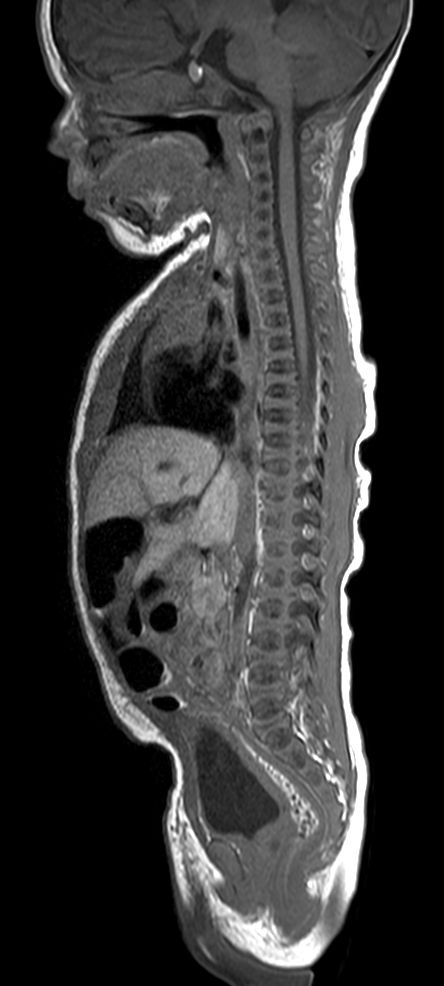

Pediatric Total Spine with spina bifida

Neonatal patient, 5 days old, with spina bifida